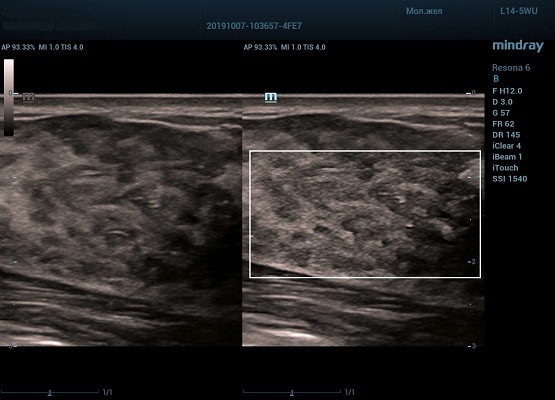

HD Scope позволяет достигать поразительной разрешающей способности выбранной зоны сканирования, при этом улучшая как детализацию, так и контрастность изображения. Помимо пространственного разрешения мы получаем преимущество и по разрешению во времени. Прибор получает огромное количество нативных изображений практически одновременно, и при сборе итоговой картины не происходит смещения объекта под датчиком, а значит и нет размывания изображения. Все участки раздела фаз, каждый контур образования теперь видны, мы все ближе к идеальной картинке.

Как он работает? Особенностью платформы ZST+, на которой построены приборы Mindray Resona, является так называемое многолучевое сканирование. В отличие от обычного датчика, который получает изображение в виде прямого эхо, датчики приборов этой серии проводят многолучевое сканирование каждым элементом с огромной скоростью, получая огромное количество данных. Затем происходит сложная постобработка и сбор из множества «многолучевых» снимков идеальной картинки.

Вторая особенность ультразвуковых машин данной линейки — это изменение расчетных констант распространения ультразвука, таким образом прибор перебирает для каждой ткани свои значения скоростей волны и пересчитывает каждую точку, делая менее выраженным поглощение по глубине. Эти особенности позволили использовать без фокусные технологии сканирования. Функция HD Scope позволяет использовать эти ресурсы для исследование небольшой области, значительно увеличивая качество изображения.